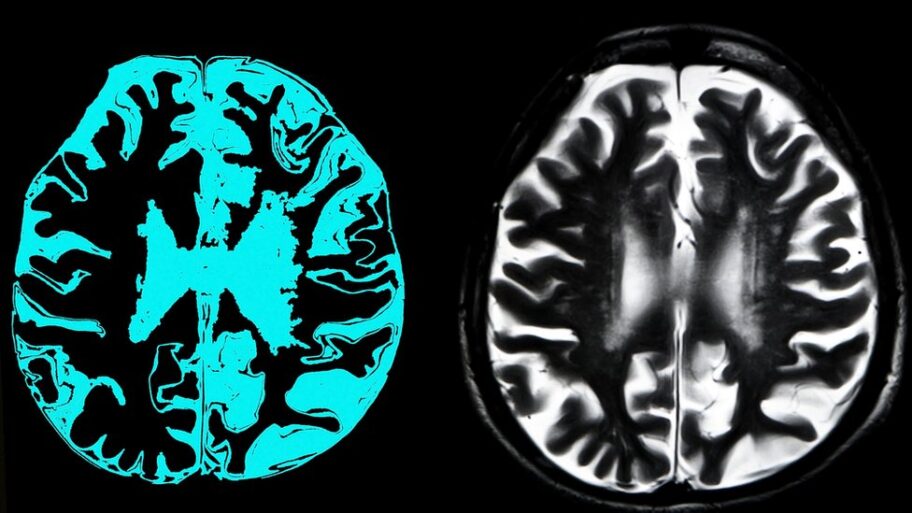

Profesionalci iz ovih oblasti imali su slične rezultate kao i drugi ljudi na testiranju moždanih sposobnosti, navodi se u rezultatima istraživanja.